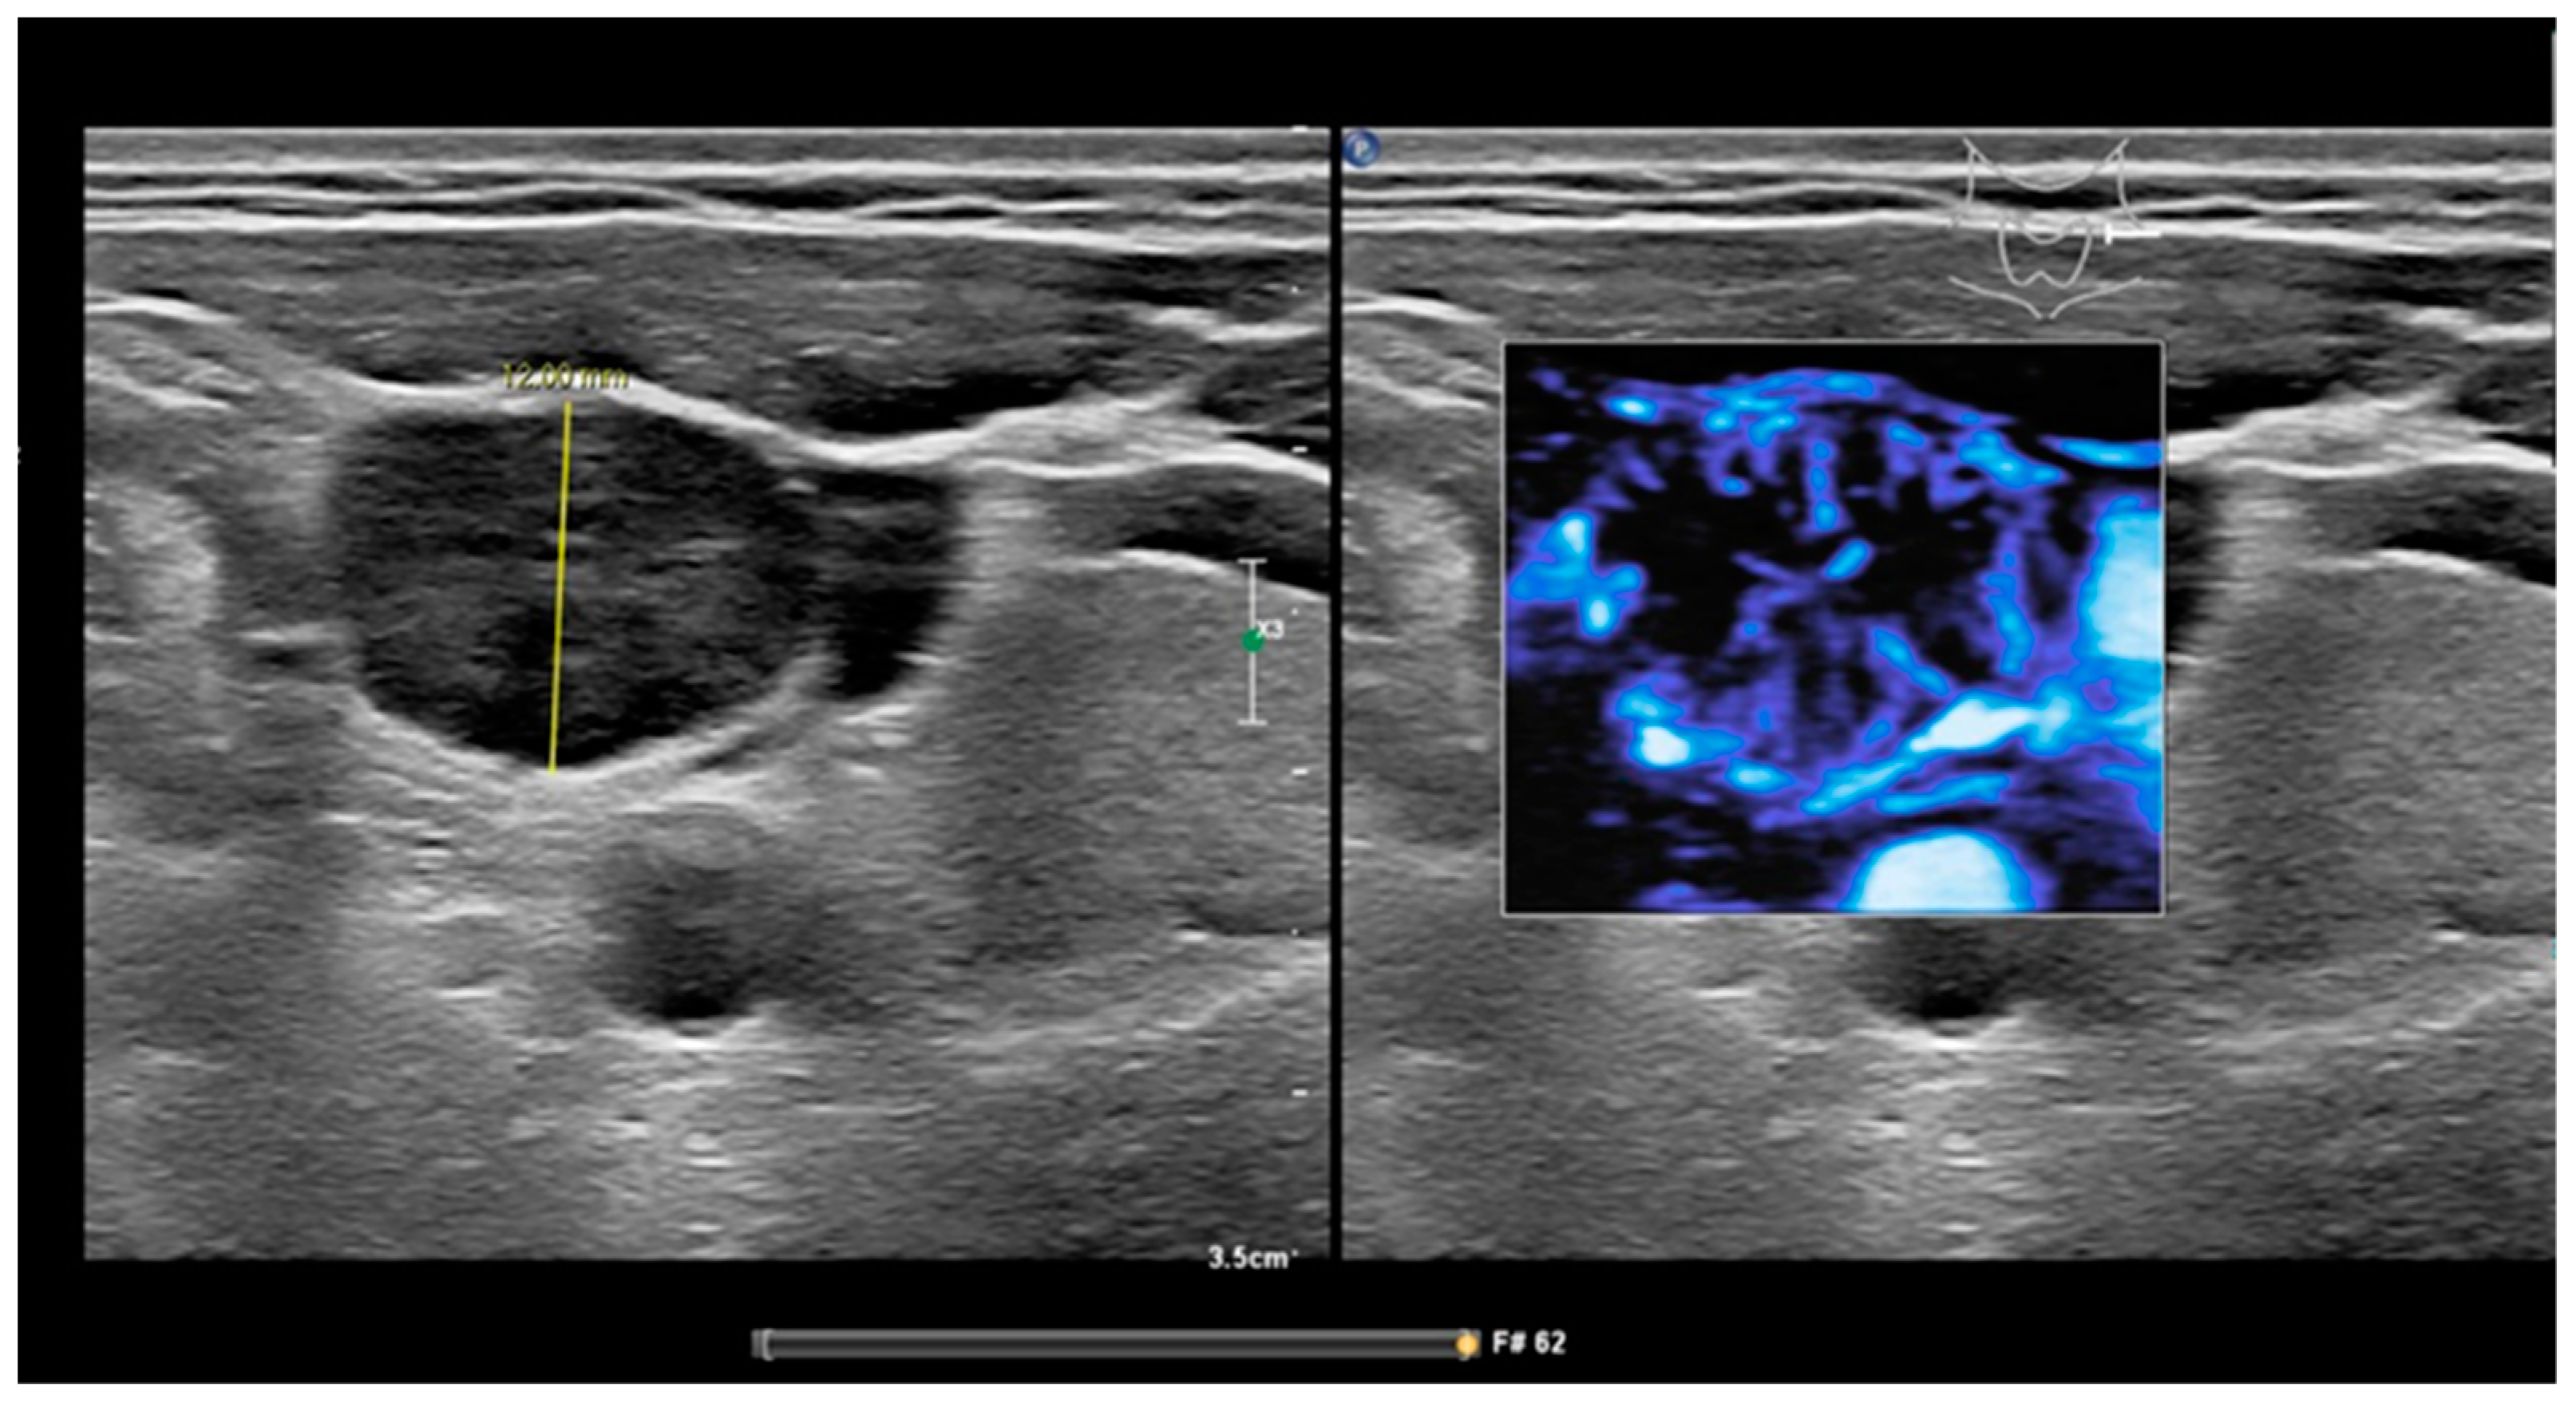

Figure 1.

MFI of peripheral vascularity in a patient with oropharyngeal SCC. At cytology metastasis SCC, MFI shows a strong peripheral vascularity which indicates malignancy; fatty hilum sign is absent.